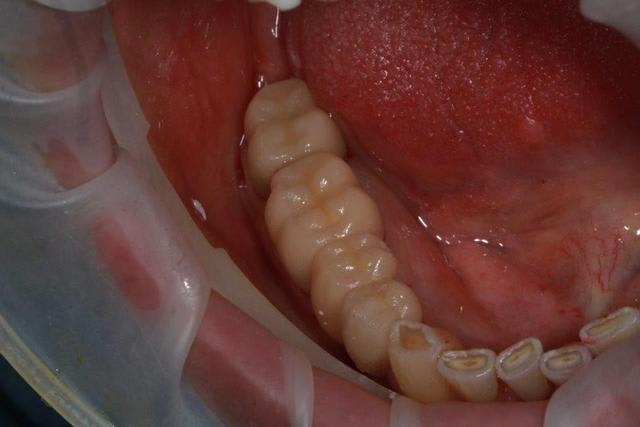

Ce matin repose d'un nouvel implant et comme je ne veux pas prendre de risque, et que les dents adjacentes doivent être couronnées, je pose un bridge en emax press, mais scellé au ciment provisoire...

Si l'implant va bien le bridge sera déposé, coupé, et 44/46 seront collées définitivement après traitement acide et silane.

Si par hasard l'implant pose problème, dépose et bridge collé.

Dépose gratuite bien sur et repose gratuite aussi, le bridge n'est pas facturé non plus, il le sera sous forme de 2 couronnes que cette fois ci l'implant fonctionne ce que j’espère, ou laissé en bridge si l'implant devait être retiré.

Le fait de scellé au ciment temporaire ne pose en principe pas de problème pour 3 à 6 mois.